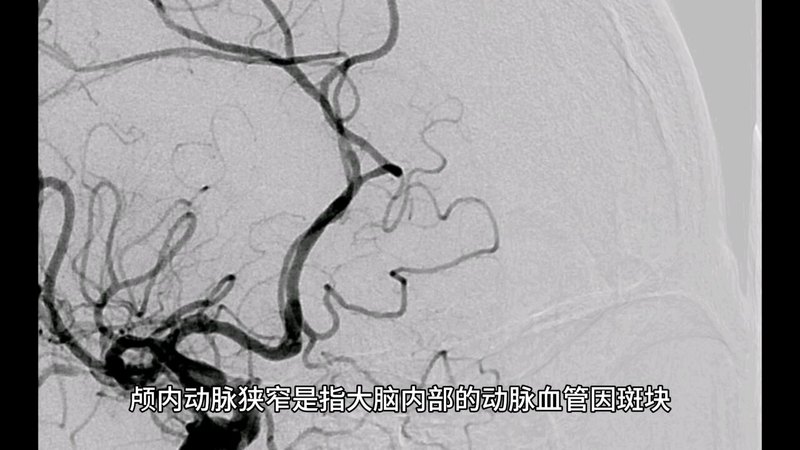

颅内动脉狭窄的诊治现状和手术策略

贾子昌副主任医师 北医三院 介入血管外科

颅内动脉粥样硬化性狭窄介入治疗的问题和挑战

张毅主任医师 东南大学附属中大医院 介入与血管外科